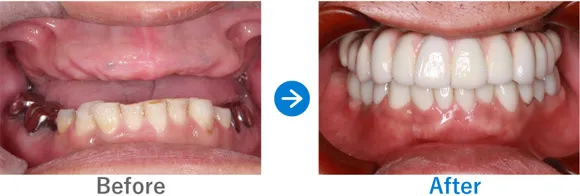

Case3

重度の歯周病を罹患された方。フルマウスインプラント治療直後に仮歯が入り感動されたケース

全顎上下共にブリッジ治療されている。重度の歯周病で歯がグラグラしている。

上下、ALLON4

5,884,000円(上下総額/内訳:上顎オールオン4(ノーベルインプラント4本)、下顎オールオン4(ノーベルインプラント4本)、3Dモデルガイド*、仮歯、セデーション、ボツリヌストキシン注射、3D模型、保証10年)

来院の背景

全体的に重度の歯周病に罹患しており、歯がグラグラしており抜けそうで咬めない、食事ができなく困っていた。インプラントを検討していたが他院で800万円〜900万円と聞いた。デンタルローンを申請。

治療結果

上下のALLON4を実施して治療同日に上下手術を行った。治療後すぐに仮歯が入ったので、とても喜んでいただいた。治療終了。メンテナンス来院継続中。

現在、セルフケアもしっかりされていて、メンテナンスも欠かさず来院していただいているため、インプラントは問題なく使えています。先日、横浜院で10年ぶりくらいにお会いしたのでご挨拶したら、とても喜んでくださりました。あの時インプラントの決断をして良かったと仰っていました。